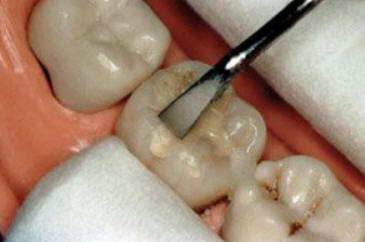

Imagen digital que representa la microfiltración y penetración del sellante realizado.

Microfotografía: Muestra como el sellador obtura la caries subyascente, evitando su avance.

Código 3 (Caries moderada) in vitro. Los códigos 3 in vivo debe ser sellado para evitar el avance del proceso carioso. (MNO)

Código 4 (Caries moderada) in vitro. Los códigos 4 in vivo deben ser tratados en forma operatoria con preservación dental (MOPD), porque presentan dentina infectada.